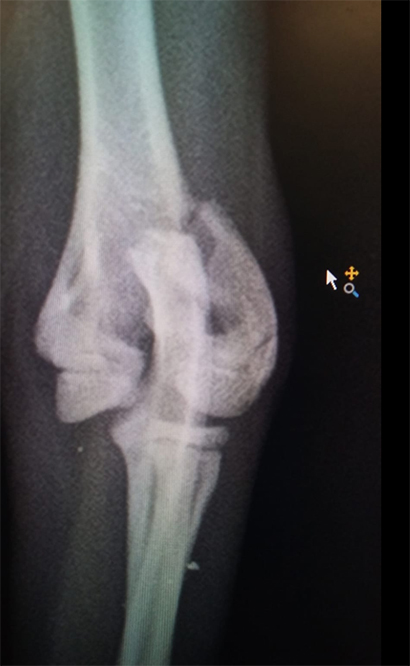

Dort wurde der junge Mann untersucht und es stellte sich heraus, dass der Sturz zwei schlimme Trümmerbrüche, einen im Vorder- und einen im Hinterbein, nach sich gezogen hatte.

++klick für groß++